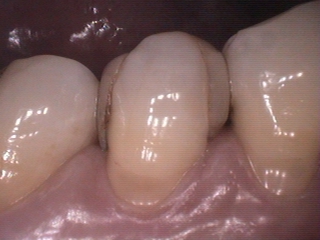

セレックでスキャンして、入れてもらったのがこちら。↓

上からみると口腔内カメラで撮っても境目もわかりませんよね。

横から見ると。。。